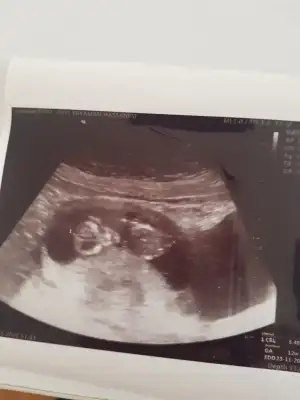

Aynen daha iyi ise usg net tahmin edilirEn net olan buydu ama yarın tekrar kontrolüm var 12+4 olacak olmazsa onu atarım![]()

Net değil sanki erkek gibi siz yinede 12-13 hafta usgde paylaşın11+3 günlük gebeyim rica etsem babada cinsiyet tahmini yapabilir misiniz?

Erkek gibi 12-13 hafta olursa paylaşın11+1 yorumlar mısınız![]()